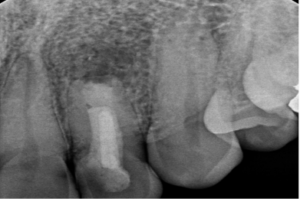

After 11 months, we’re thrilled to report significant improvements:

- Resolution of the apical lesion

- Acceptable healing around the root tip

- No tenderness or discomfort

While the outcome isn’t perfect, it’s a remarkable success given the tooth’s history and condition.